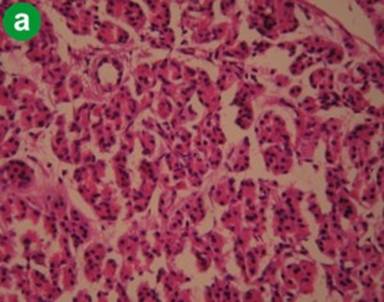

Adenocarcinoma of the Pancreas

H&E staining showed poorly oriented cells infiltrating singly, to solid sheets of neoplastic cells, ductal proliferation, clusters of proliferative acini with loss of lobular architecture, invasive adenocarcinoma, nuclear pleomorphism, necrotic debris and increased stroma, in variable combinations and frequency (Figure 3a). Immunohistochemistry with α-SMA showed dense and diffuse staining pattern in areas of fibrosis, denser in visual impression compared to tropical calcific pancreatitis and alcoholic chronic pancreatitis (Figure 3b). Staining with CD34 showed no or sparse positivity in the areas of fibrosis, but staining was present in blood vessels and ducts (Figure 3c). These findings suggest that activated stellate cells are diffusely present in the areas of desmoplasia.

Figure 3. Representative staining pattern observed in cases of adenocarcinoma of pancreas (a. H&E, b. α-SMA, c. CD34). |